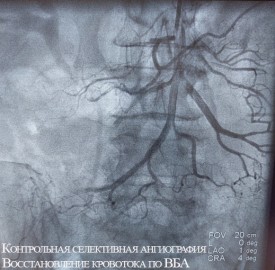

Обеим женщинам было выполнено эндоваскулярное вмешательство — без разрезов, через прокол в бедренную артерию в паху был введен зонд, с помощью которого врачи удалили тромбы из просветов сосудов. Обе пациентки были в сознании во время операции, и прямо на операционном столе у них прошел болевой синдром.

Оперировал обеих больных эндоваскулярный хирург Нарек Вачаганович Марукян. Первая пациентка была выписана на третий день после лечения. Перед этим ей выполнили коронарографию (поскольку поступила она с подозрением на инфаркт), при этом вмешательство на сосудах сердца не потребовалось. Вторую больную выписали на амбулаторное лечение через неделю после операции.